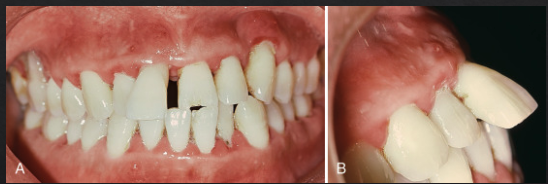

what’s pathologic tooth migration

form of secondary occlusal trauma: normal occlusal forces acting on reduced periodontium → tooth mobility + migration

4 clinical signs of pathologic tooth migration

periodontitis

increased mobility

new interproximal gaps

tooth extrusion